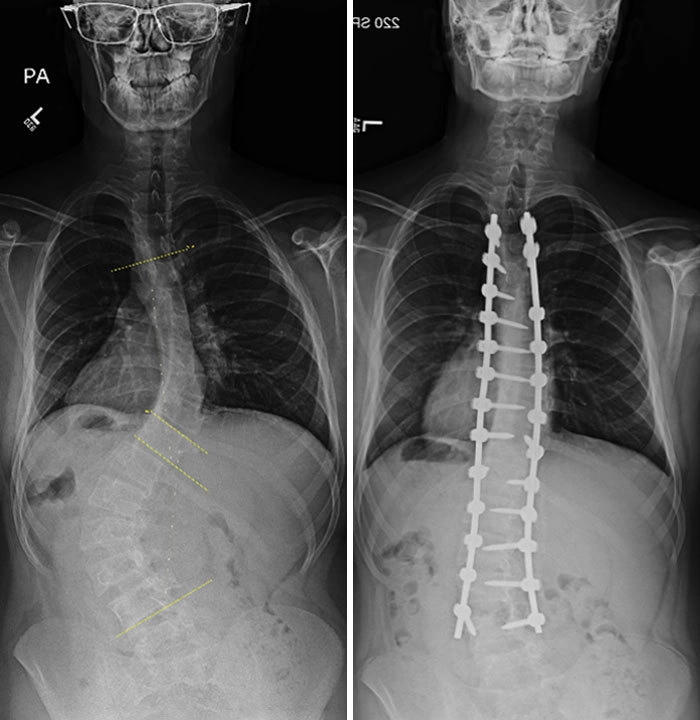

Сколиоз на рентгене до и после операции